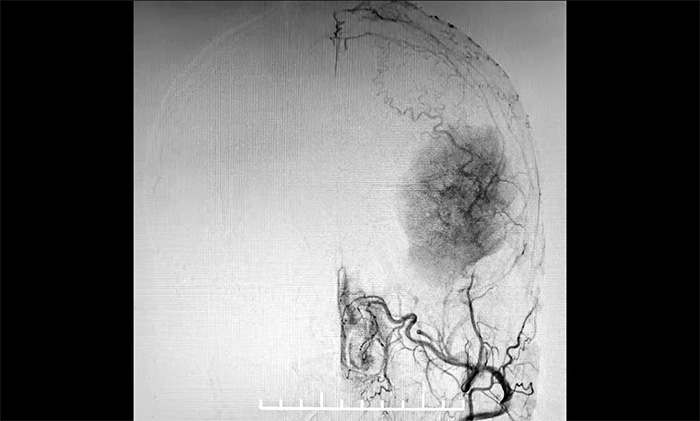

发生于额颞部位的巨大脑膜瘤,治疗方法主要为显微外科手术切除。该肿瘤不仅体积巨大,横跨多个重要脑功能区,行DSA检查发现,肿瘤包裹缠绕多根重要的动脉血管,血供十分丰富。若直接行手术切除肿瘤,容易因术中大出血而危及患者生命。

▲ DSA检查示:肿瘤血供丰富